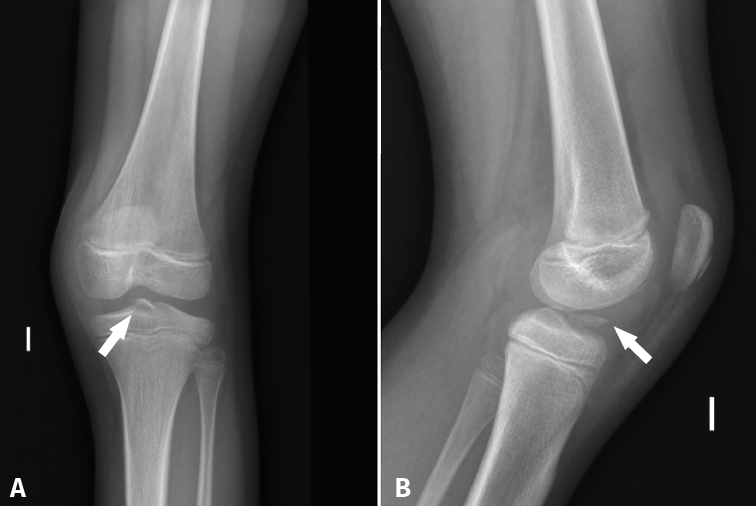

Although the findings are usually normal, plain radiographs can help discard other types of lesions. Tibial spine fracture (Figure 2) in children can occur with a clinical history and physical examination findings similar to those of ACL injuries(26). In addition, radiographs allow us to assess other lesions (epiphysiolysis, fracture-avulsion of the inferior pole of the patella or fractures of the tibial tuberosity) characteristic of pediatric patients(27). Therefore, anteroposterior under loading and lateral Rx views of both knees are needed in the case of suspected ACL injury.

Figure 2. Radiographs of the left knee in anteroposterior (A) and lateral (B) view in a 10-year-old boy, showing tearing of the displaced anterior tibial spine (arrow), corresponding to grade II of the classification of Meyers and McKeever.